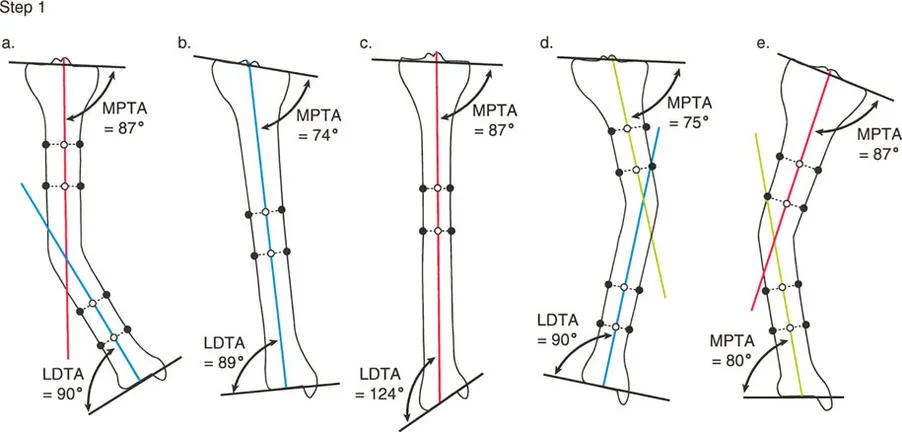

في المستوى السهمي، يجب أن تكون هناك زوايا محددة بين محاور العظام وخطوط المفصل لضمان توزيع متوازن للوزن واستقرار الأربطة. هذه الزوايا هي حجر الزاوية في مبادئ الدكتور بالي لتصحيح التشوهات:

- زاوية الفخذ الخلفية البعيدة (PDFA): وهي الزاوية بين المحور التشريحي لعظم الفخذ وخط مفصل الفخذ البعيد في المستوى السهمي. قيمتها الطبيعية حوالي 83 درجة.

- زاوية الظنبوب الخلفية القريبة (PPTA): وهي الزاوية بين المحور التشريحي لعظم الظنبوب وهضبة الظنبوب. تتراوح قيمتها الطبيعية بين 81 و 84 درجة.

توضح الصورة المحاور التشريحية والزوايا الطبيعية لعظم الفخذ والظنبوب، والتي تُعد أساساً لفهم تشوهات الركبة السهمية.

يتطلب التخطيط السليم تحديد خطوط العظام الطويلة وحساب قمة التشوه بدقة. وكما هو الحال في مبادئ محاذاة المحور، فإن تحديد خطوط منتصف العظم بالنسبة لخطوط توجيه المفصل هو الخطوة الأولى في تحديد مركز دوران الانحراف (CORA)، وهو النقطة التي يجب أن يتم عندها قطع العظم لتصحيح التشوه.